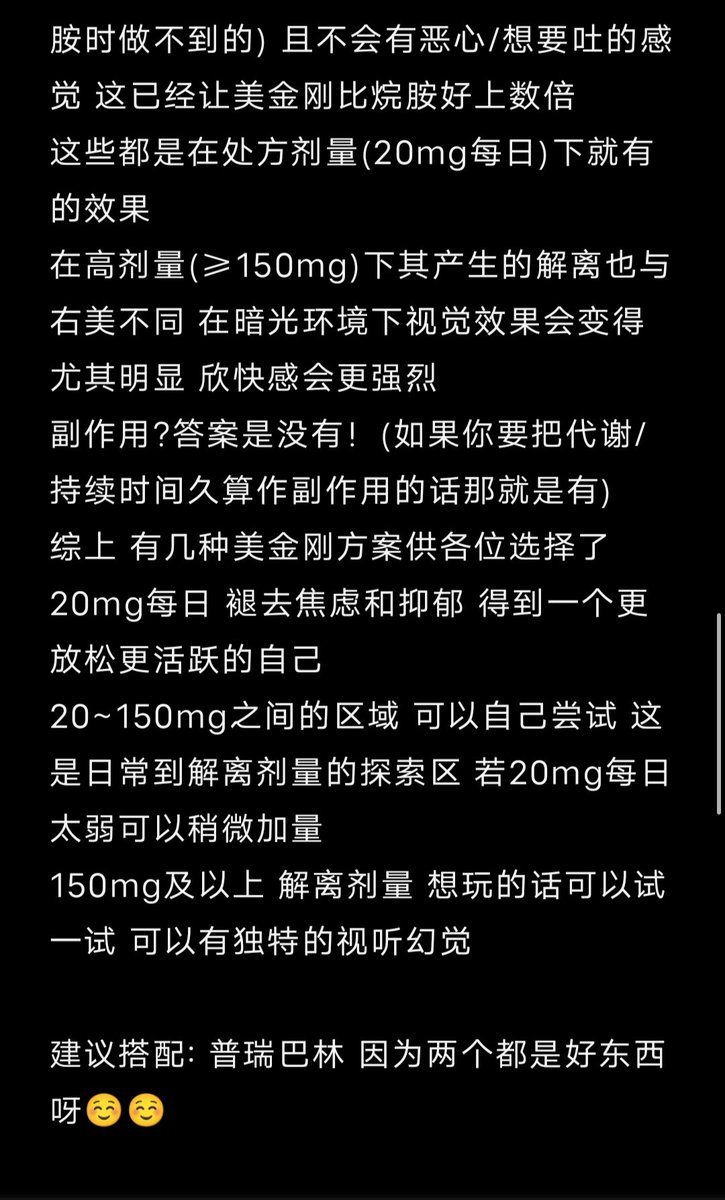

金刚烷胺会对神经系统造成长期/不可逆的影响

首先多巴胺系统

金刚烷胺作为多巴胺释放促进剂,在长期使用或过量下可能导致:

-DA系统适应性衰竭(Receptor downregulation)

-药源性多巴胺枯竭综合征:表现为认知退化、动机缺失(apathy)、情绪迟钝等。

NMDA

虽然金刚烷胺是弱NMDA拮抗剂,但长期使用可能导致:

-突触可塑性损伤(LTP/LTD受阻)

-情景记忆下降、学习能力减退

-焦虑、攻击行为升高

-神经元代谢负荷增加,增加兴奋毒性风险

金刚烷胺提高兴奋性毒性(NMDA活性失衡、多巴胺代谢紊乱),与致幻剂合用或交替用药会:

-加剧皮层-边缘系统的不稳定性(例如海马体、前额叶)

-增加精神病风险(psychosis risk)

-导致长期认知损伤与感知畸变的残留症状(HPPD-like states)

另外有导致神经适应性结构改变

动物研究提示,金刚烷胺长期使用可能导致:

-树突棘数量下降

-突触可塑性衰退

-神经炎症因子(如IL-6)升高,为不可逆脑损伤打下基础

炽烈已极 @AnIncandescence并且,它可能会导致以后使用娱乐药物时的负面效应

2025-04-29 11:45:39 UTC

简版

金刚烷胺不但无法提供真正的致幻体验,反而会破坏大脑、干扰神经系统,带来无法逆转的损害。

短期风险:

-幻觉质量差、碎片化,常伴恐惧、迷惑、妄想

-谵妄状态(严重的意识混乱)

-焦虑、失眠、暴躁、攻击性升高

-心跳紊乱、口干、头晕、甚至癫痫发作

长期风险:

-损伤大脑中的多巴胺与谷氨酸系统

-学习能力下降、情绪变平淡、认知迟钝

-增加患上药源性精神障碍的风险

炽烈已极 @AnIncandescence金刚烷胺会对神经系统造成长期/不可逆的影响